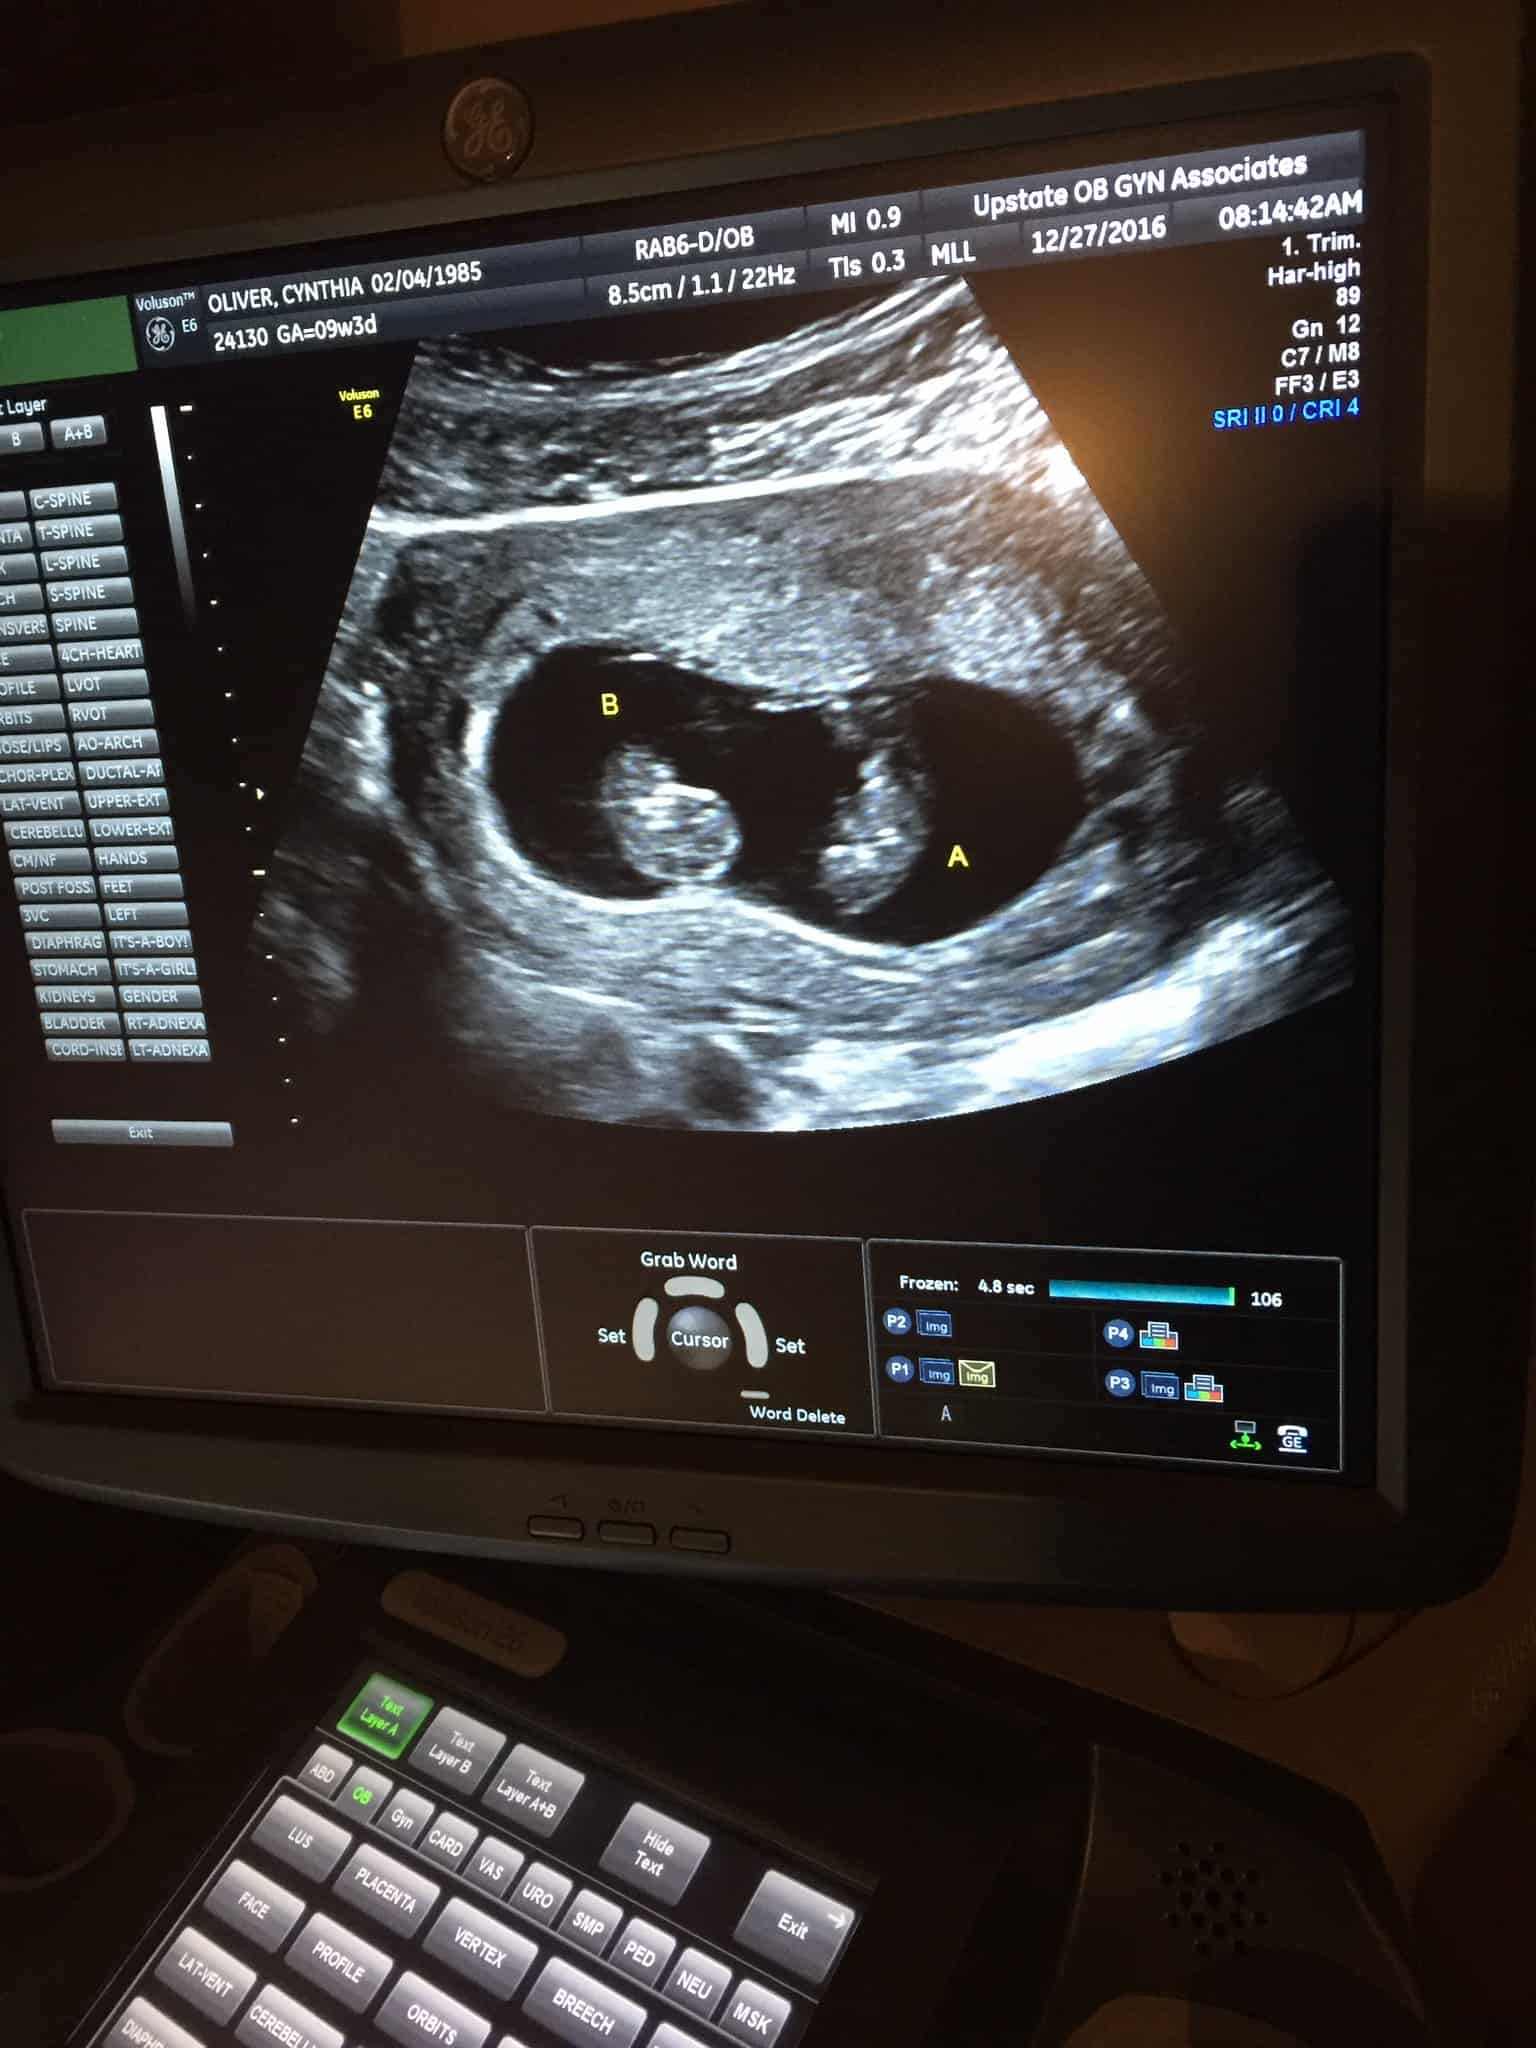

Ultrasound Photos at 30 Weeks Pregnant With Twins